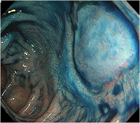

1. 患者背景、臨床症状からCMV腸炎を疑う場合は、組織採取が行える内視鏡検査が勧められる(推奨度1)

1. CMV腸炎診断のための内視鏡検査は、深部大腸まで観察し、潰瘍だけでなく、びらん、発赤、などの粘膜変化からも生検することが勧められる(推奨度2)